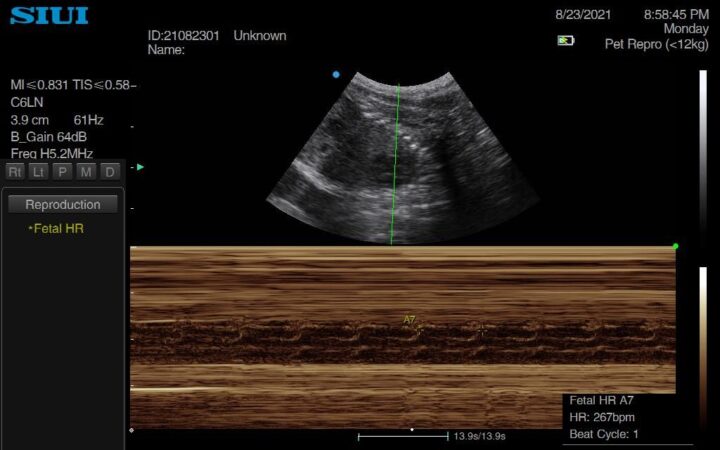

In more mature pregnancies, you may also wish to calculate the foetal heart rate – particularly if worried about foetal distress – which can be performed using either M-mode (Figure 5) or Doppler. Pulsed wave Doppler can also be used for more advanced measures, such as calculating the resistance index, which can predict whelping time in dogs. Again, making comments on foetal heart rate is only within the remit of a veterinarian, and is another way to demonstrate expertise.